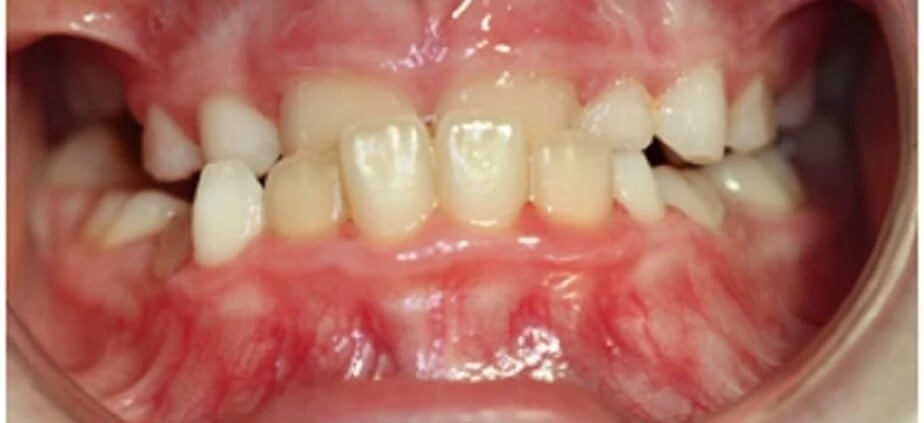

La mordida cruzada anterior se presenta como una maloclusión que altera la alineación habitual de los dientes.

- En la mordida cruzada anterior, los incisivos superiores ocluyen por dentro de los inferiores, mientras que en la sobremordida, los dientes superiores cubren excesivamente a los inferiores.

- Evaluación clínica y examen oclusal: El ortodoncista realiza un examen visual para observar la alineación dental y la forma en que los dientes superiores e inferiores encajan al cerrar la boca.

- Análisis fotográfico y registros para seguimiento: Se toman imágenes de los dientes, la sonrisa y el perfil facial del paciente útiles para documentar cambios a lo largo del tratamiento.